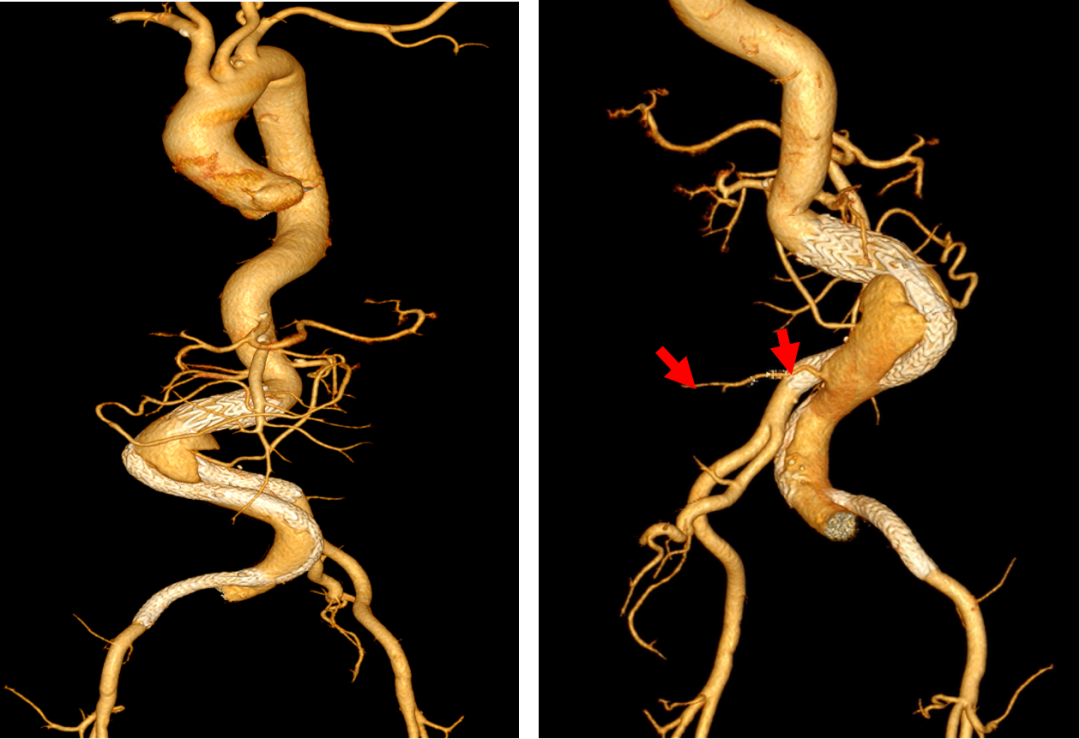

术后三天出现了严重并发症,患者出现II型内漏,推测主要来源于未彻底封堵的髂内动静脉瘘;同时,患者右侧肢体进行性无力,小腿肌肉瘫痪,肌力降为0级,膝关节、踝关节功能受限,小腿外侧及足部感觉丧失,这是髂内动脉封堵后引发的臀肌缺血症状。

术后CT